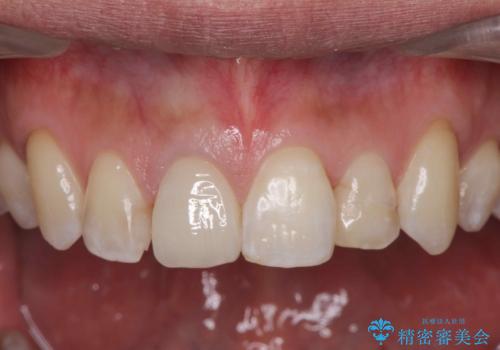

前歯の並びが改善し、色調の気になっていたクラウンの審美性も大きく改善することができました。

当法人では一つの医院で、矯正治療とセラミック治療を行うことができます。